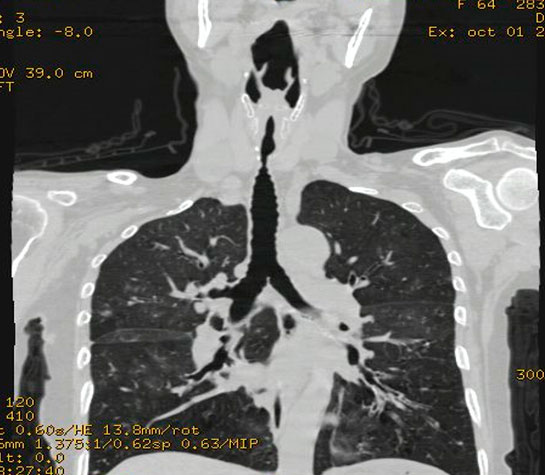

Las estenosis traqueales (obstrucción de la vía aérea) en adultos y niños es una patología que compromete gravemente la vida de los pacientes siendo la más frecuentes la causada por la intubación prolongada, en los últimos años con la pandemia del COVID 19 donde tuvimos un gran número de personas intubadas en UCI por mucho tiempo, aumento muchísimo el número así como la severidad de los casos de estenosis traqueal y fistula traqueoesofágica (comunicación anormal entre el esófago y la tráquea), estos problemas al comprometer la via aérea y la via digestiva son muy graves y si no son tratados adecuadamente (tratamientos no adecuados) conllevan alto riesgo de complicaciones.

Estenosis Traqueal